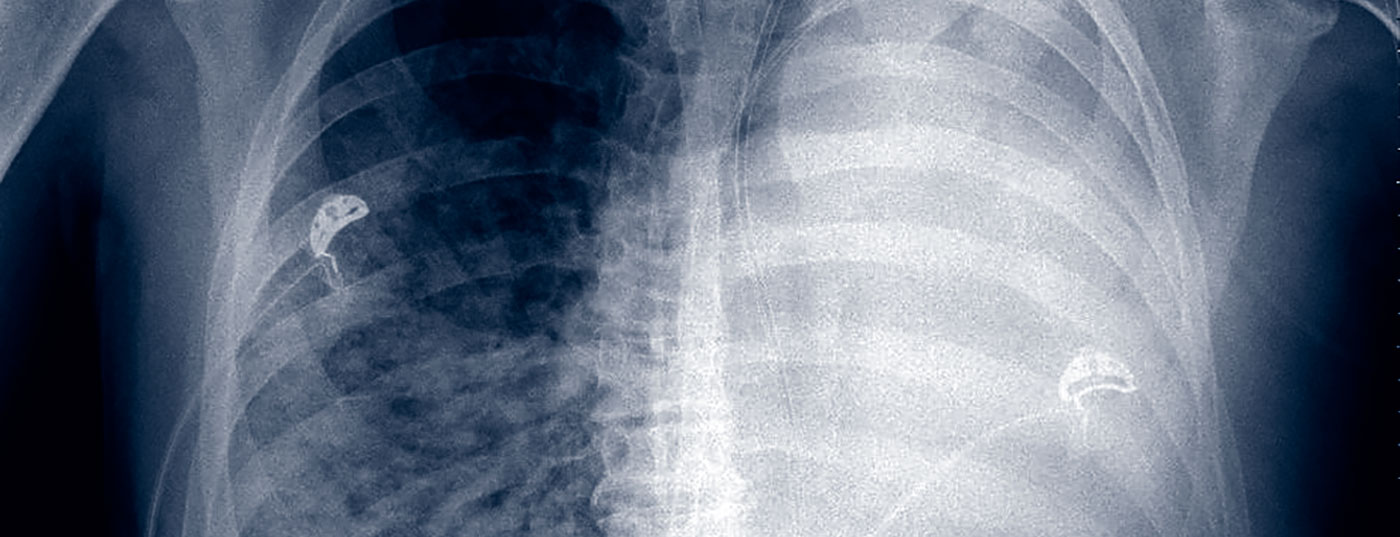

Jede Operation kann postoperativ zu Problemen mit dem Kreislauf, dem Herz oder an der Lunge führen. Der Vermeidung solcher Komplikationen und deren Behandlung kommt eine grosse Bedeutung zu, denn sonst erhöht sich das perioperative Risiko deutlich. Dazu ist es erforderlich, dass ein Behandlungsteam in der Thoraxchirurgie die intra- und postoperativen Risiken kennt und die Behandlung der dabei auftretenden Komplikationen beherrscht.